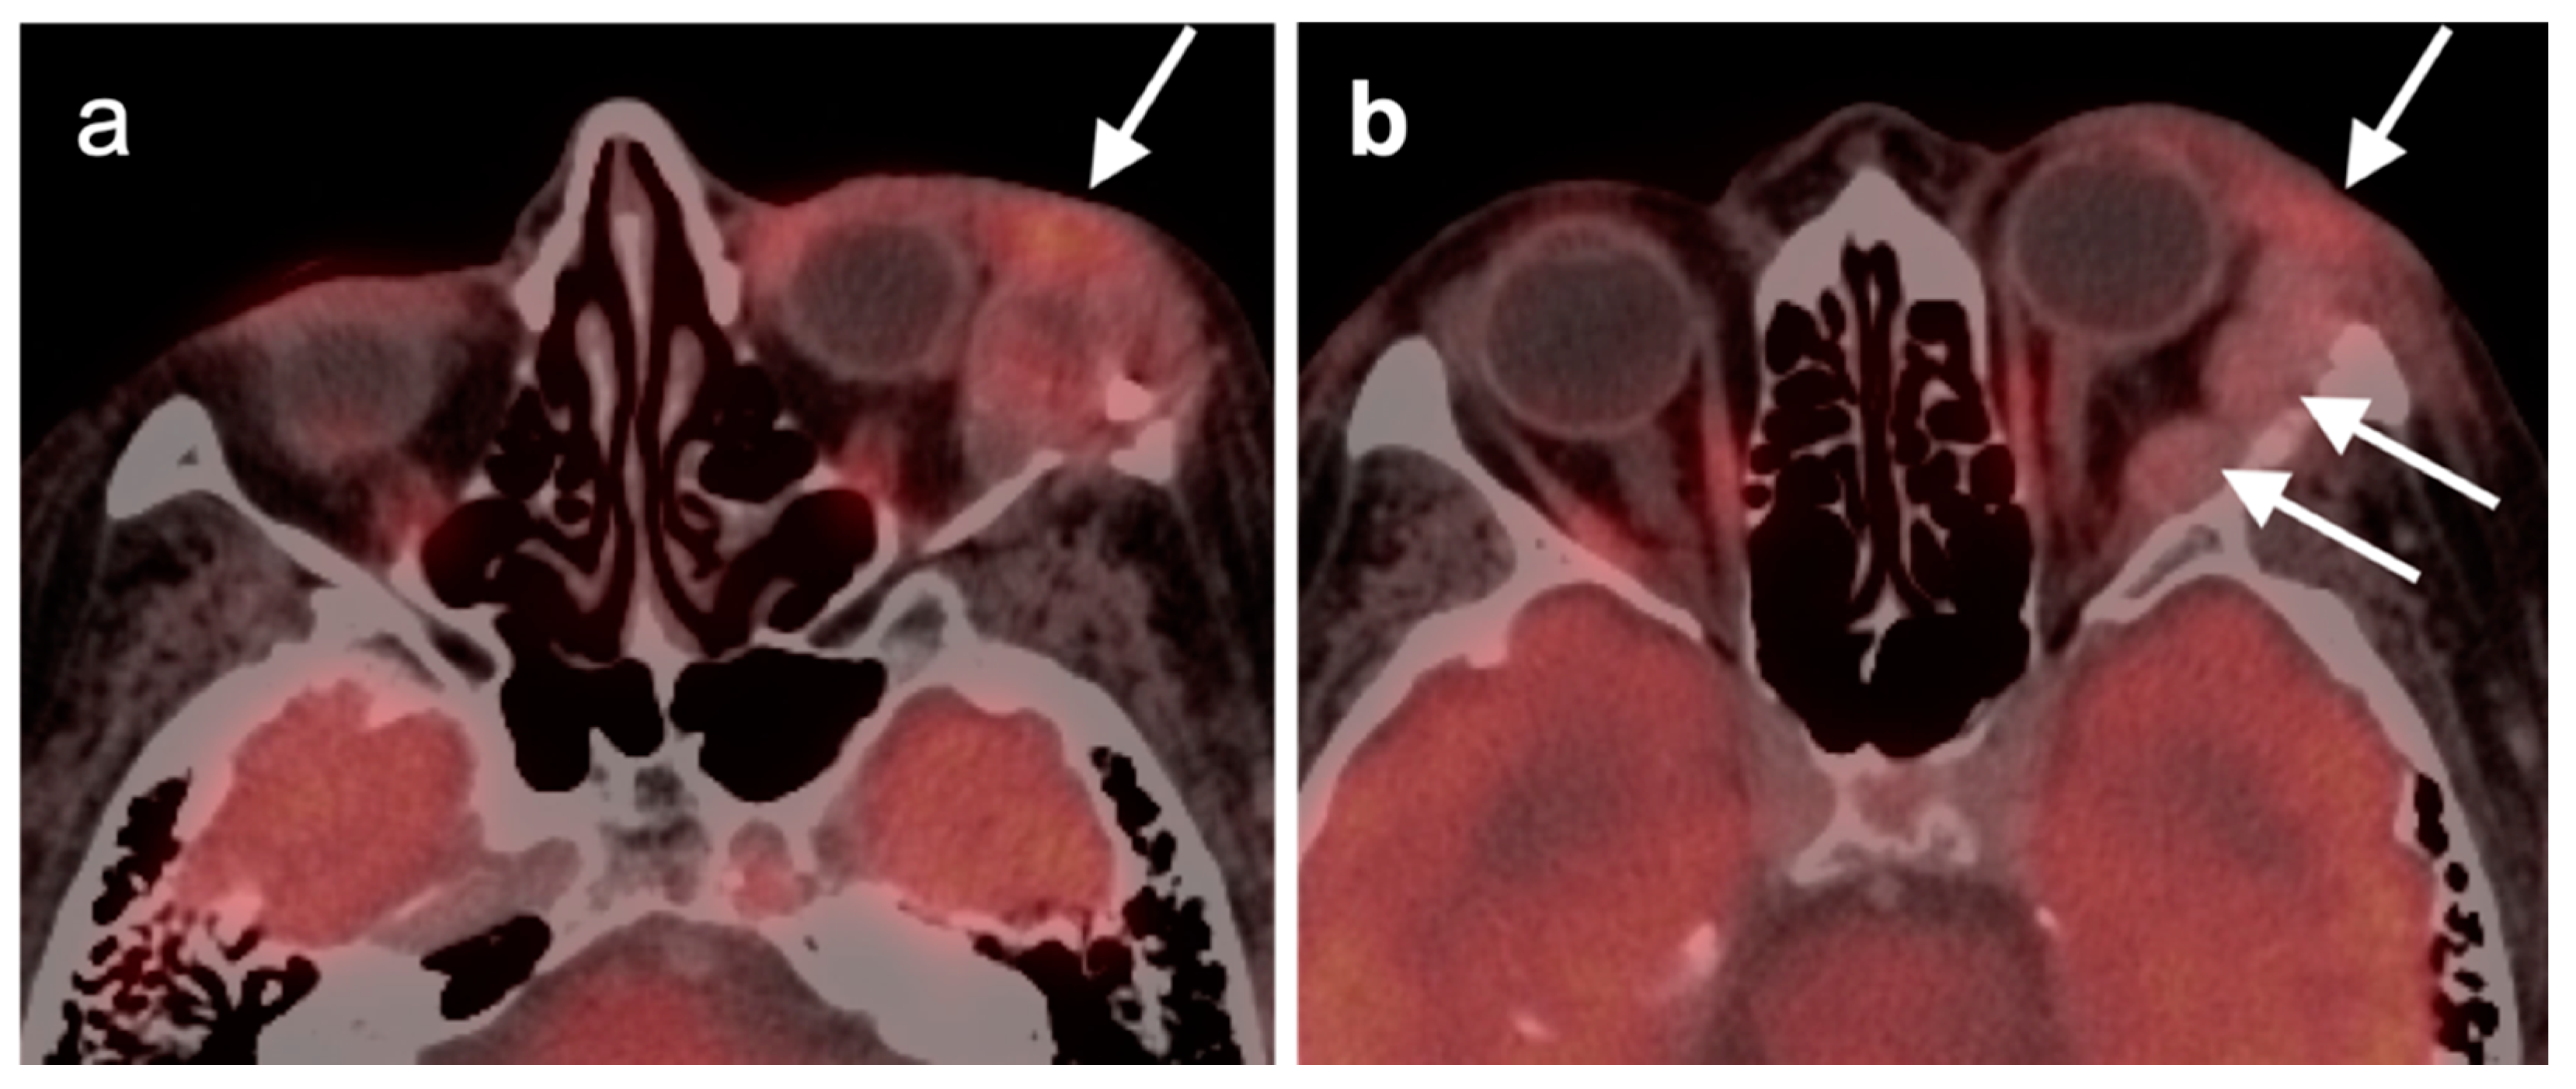

2.5. Major and Minor Salivary Gland, Lacrimal Gland Tumors

- Pleomorphic adenoma and carcinoma ex pleomorphic adenoma

- Warthin tumor